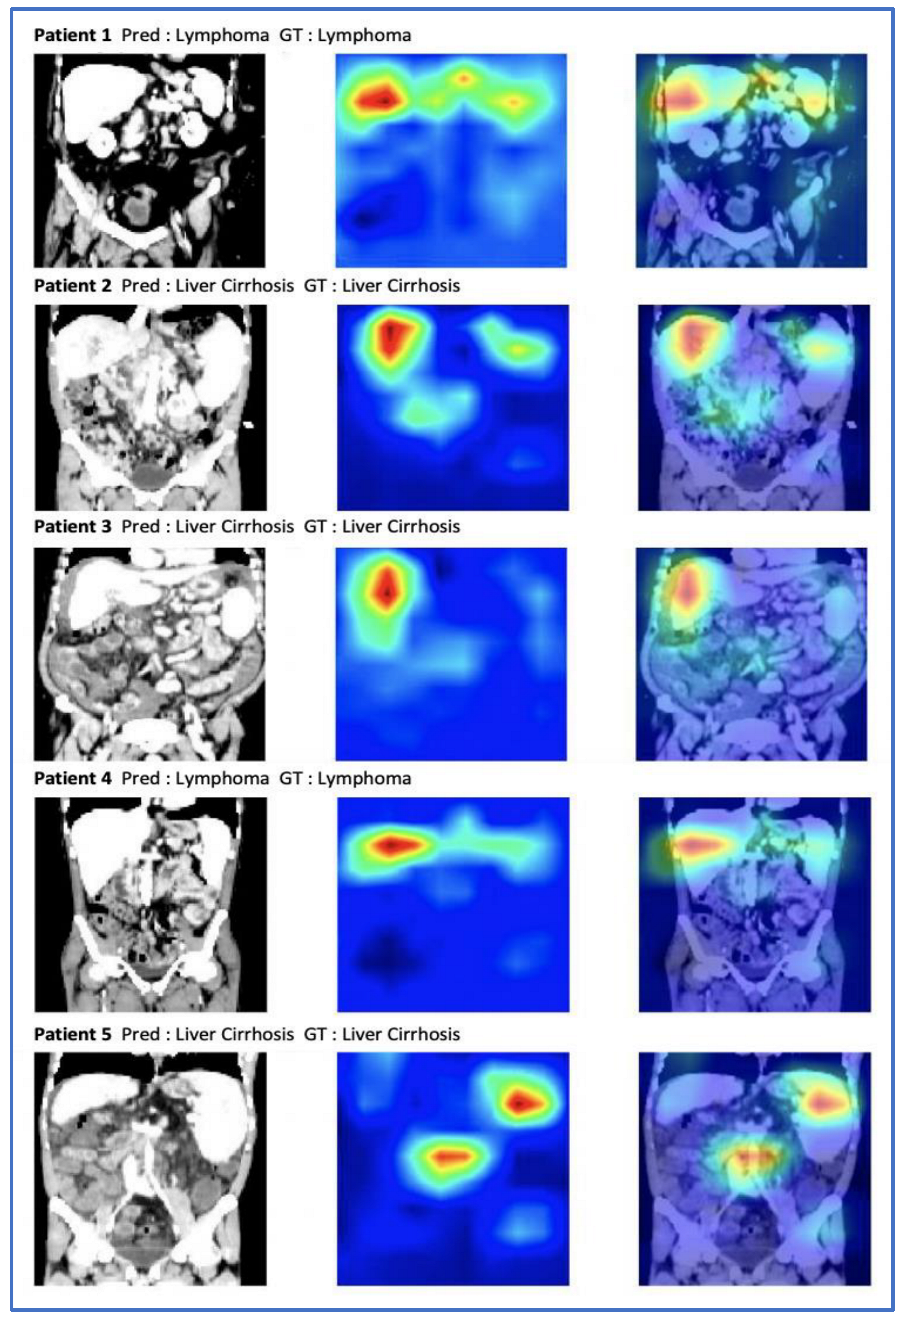

3.4. Occlusion Sensitivity Maps Visualization